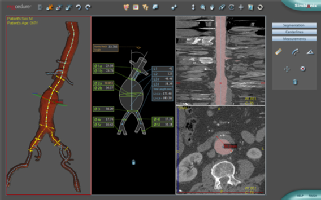

Vascular segmentation workstation

PROcedure Rehearsal Studio automatically identifies structures, segments relevant vasculature from surrounding structures, and features all the standard functionality of vascular imaging and analysis workstations, including vessel views and cross-sections.

PROcedure lets you plan, save and print the steps of your procedure for review, teaching and future use.

This unique feature automatically identifies and quantifies vessel stenosis and then displays its location, severity and dimensions.